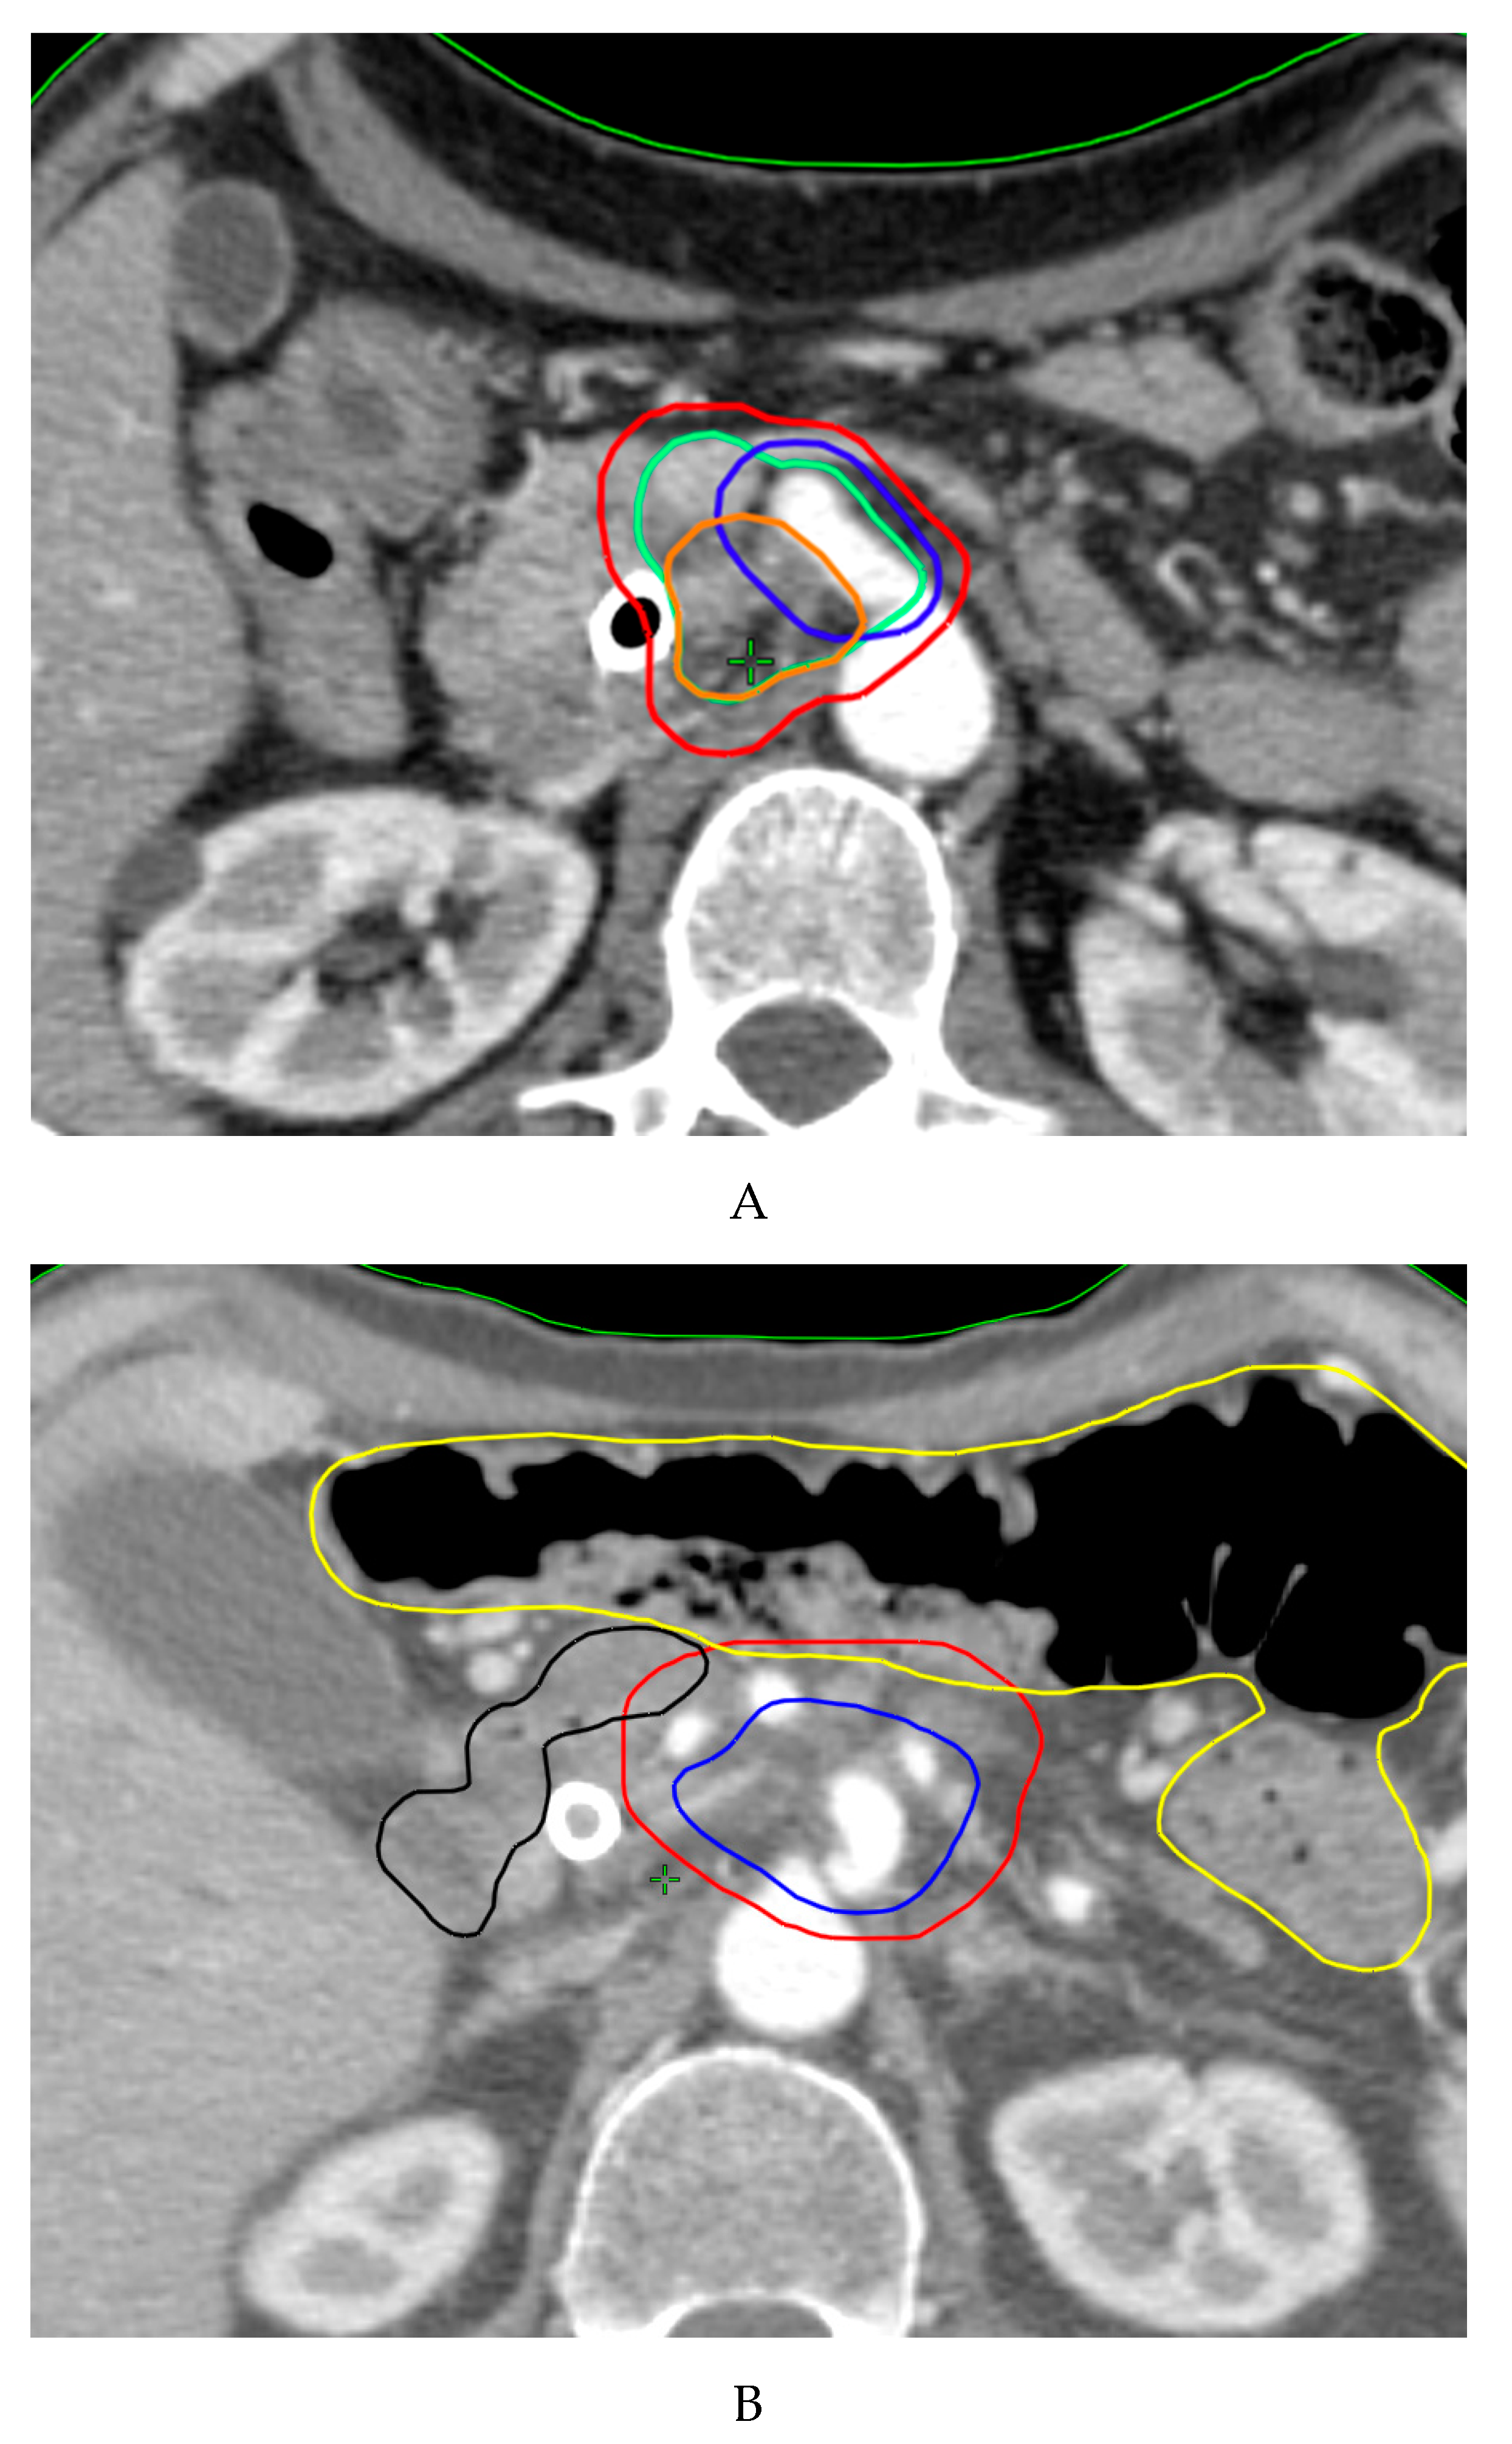

5.4. Simultaneous Integrated Boost (SIB)

| Study, Year [ref] | Study Type | Tumor Stage | Fractions (n) Tumor Target Definition | Tumor Target Dose (Gy) | SIB Target | SIB Dose (Gy) | Study Primary Endpoint | Late Toxicity G ≥ 3 | |

|---|---|---|---|---|---|---|---|---|---|

| Chuong, 2013 [147] | Retrospective | BRPC/LAPC | 5 | PTV = entire tumor + 3–5 mm | 25 | TVI (region of vessel abutment/encasement) | 35 | OS (m): 16.4/15 PFS (m): 9.7/9.8 BRPC/LAPC | 5.3% |

| Passoni, 2013 [148] | Phase II | LAPC | 15 | PTV = ITV (tumor and enlarged lymph nodes plus motion) + BTV + 5/7 mm | 44.25 | Infiltrating vessel + 1 cm within GTV | 48-58 | DLT: not reached | 0% |

| Mellon, 2015 [78] | Retrospective | BRPC/LAPC | 5 | PTV = GTV (plus motion) + 3–5 mm | 30 | TVI (areas of vessel involvement by tumor) | 40 | OS (m): 19.2/15 LCR: 78% * | 7% |

| Krishnan, 2016 [8] | Retrospective | LAPC | 28 15 | PTV = GTV + 15 mm | 50.4 37.5 | GTV + 2–5 mm | 63–70 67.5 | OS (m): 17.8 PFS (m): 10.2 | No additional compared to SDR |

| Shaib, 2016 [121] | Phase I | LAPC | 3 | PTV = GTV with at-risk area of microscopic spread + 5 mm | 12 | PM = volume between the posterior 1 cm of GTV and mesenteric vessel/retroperitoneal soft tissue | 15 | DLT: not reached | 0% |

| Murphy, 2018 [149] | Phase II | BRPC | 28 | PTV = CTV (GTV + 1 cm margin and elective nodal coverage) + 7 mm | 50.4 | TVI (tumor involvement of critical blood vessels) | 58.8 | R0 resection rate: 97% | 0% |

| Murphy, 2019 [150] | Phase II | LAPC | 28 | PTV = CTV (GTV + 1 cm margin and elective nodal coverage) + 7 mm | 50.4 | TVI (tumor involvement of critical blood vessels) | 58.8 | R0 resection rate: 81% | 0% |